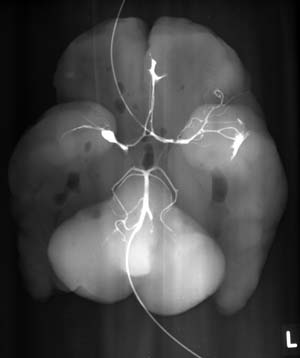

1. Идём в рентгенкомнату. Нижнюю половину гол. могзга кладём на срез на рентгеновскую кассету, покрытую обычной полиэтиленовой белой плёнкой.

2. Берём тонкий сосудистый катетер и вводим в A.vertebralis, фиксируем сосуд от соскальзывания на катетере обычной лигатурой.

3. Начинаем нагнетать под контролем зрения сульфат бария 1-3 мл. Как только воздух выходит из противоположной А vertebralis, накладываем вторую лигатуру на неё чтобы контрастное вещество не выходило. Продолжаем нагнетать бариум примерно ещё 1мл. Стоп! Первый рентгеновский снимок.

Смотрим на часы. Время 11.10

1. На снимке обычные сосуды. Communicans posterior частично заполнены барием. Ничего не нашли!

2. Берём второй эластичный катетер и вводим его во внутреннюю сонную артерию. Всё также по схеме. Стоп! Второй снимок. Есть попадание! Справа аневризма. (см. фото)

Смотрим на часы. Время 11.15

На рентгеновском снимке виден выход контрастного вещества и на левой стороне гол. мзга (на фото справа) на месте пересечения артерий на плоскости распила/разреза. Это артефакт, но он не мешает рассмотреть сами артерии.